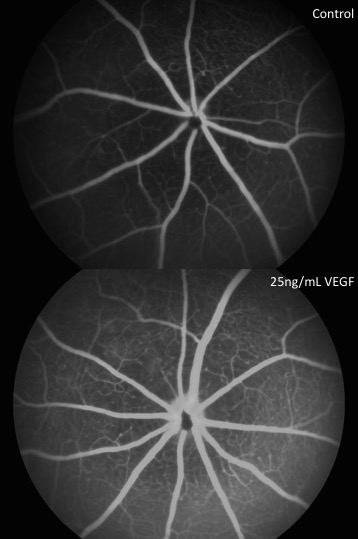

Vascular Permeability

Increased vascular permeability is a damaging component of diabetic retinopathy. To test whether a drug has an effect on permeability, we use one or more of several methods. We measure the extravasation of Evan's blue dye or fluorescein-conjugated dextrans from the vasculature into the retinal tissue, we examine fluorescein angiography, or we measure retinal thickness via OCT.